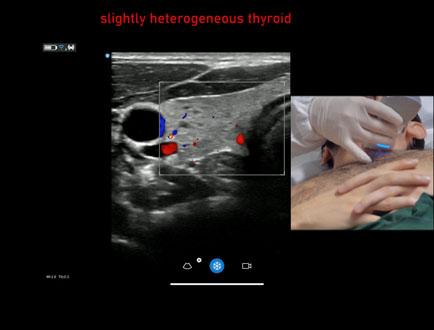

Strumento: GE Vscan Air CL

Sonda: Lineare

Età Paziente: M 30 anni

Motivazione dell'esame: tecnica ecografica con monosonda GE Vscan Air CL.

Commento all'esame: le immagini ed il video documentano i lobi tiroidei a morfovolumetria normale ed ecostruttura lievemente disomogenea. Vascolarizzazione normale.

Conclusioni: tiroide lievemente disomogenea (slightly heterogeneous thyroid).